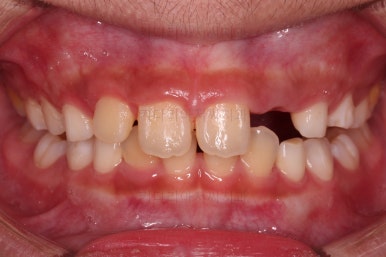

전후사진을 비교해 보겠습니다.

왼쪽이 부산어린이돌출입교정 치료 전, 오른쪽이 치료 후 입니다.

위치가 나빴던 앞니가 제위치로 갔고, 위아래 앞니도 서로 가까워졌어요.

앵글씨 2급 부정교합이 개선된거죠.

아래턱-위턱이 차이날 때 필연적으로 생기는 과개교합(앞니가 서로 깊게 맞물리는 교합)도 개선되었고요.

입이 튀어나와 보이던 모습도 완벽히 개선되었어요.

아래턱이 작아보이던 모습독 개선되었고 입도 편안하게 다물어져요.

턱의 위치가 잘못되어 결과적으로 보이던 "입이 튀어나온 모습, 윗니가 튀어나온 모습"이 턱뼈의 위치를 바로 잡아줌으로써 개선이 된거죠.